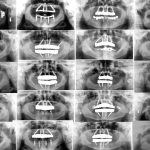

Dr. Vladimir Malušev Oral Surgeon

Dr. Vladimir Malušev is a Specialist in Oral Surgery (University of Belgrade) and an active member of the International Team for Implantology (ITI). He is a cofounder and lead clinician at White Clinic Belgrade. With a passion for Graft Free Implantology, he is dedicated to providing patients with minimally invasive dental solutions.